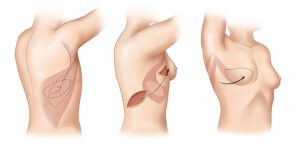

إعادة بناء الثدي باستخدام الغرسات هي جراحة تهدف إلى استعادة شكل الثدي باستخدام غرسة ثدي. وتُجرى هذه الجراحة في الأغلب بعد جراحة استئصال الثدي التي

جراحات أورام الثدي مش معناها إزالة الثدي بشكل كامل! في المراحل الأولى من أورام الثدي بنلجأ لتقنية الاستئصال التحفيظ او استئصال تجميلي للثدي اللي بيتيح